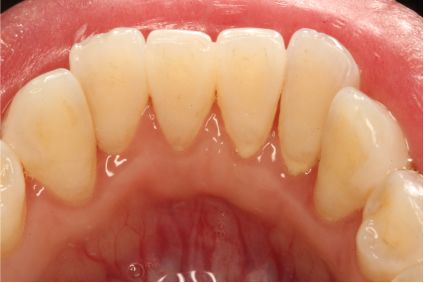

采用PT5牙周治疗仪进行全口超声龈上洁治术、超声龈下刮治术。术后5周复查可见牙龈炎症明显减轻,仍有轻度炎症,复查发现患者口腔卫生维护欠佳,再次进行口腔卫生宣教。

超声洁刮治术后5周